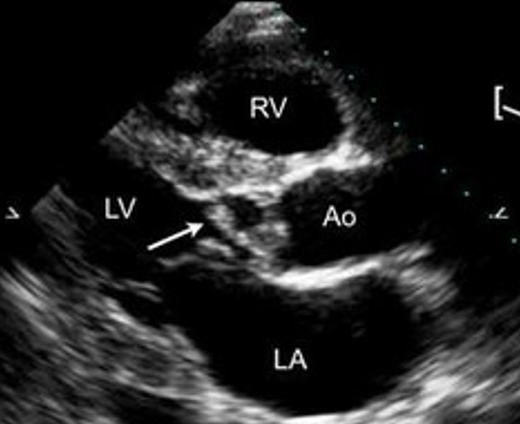

what is seen here?

tricuspid valve vegetation w/ severe regurg